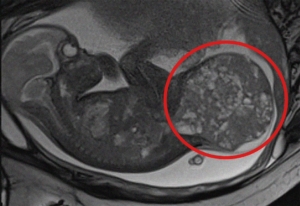

La spina bifida aperta è una delle più gravi malformazioni congenite del tubo neurale: durante lo sviluppo fetale la colonna vertebrale non si chiude correttamente e parte delle strutture nervose può rimanere esposta o non protetta come dovrebbe. Le conseguenze, spesso, accompagnano il bambino per tutta la vita. Non si tratta soltanto di un difetto “anatomico” da correggere: il punto centrale è il possibile danno neurologico, che può tradursi in limitazioni motorie e sensoriali, difficoltà nel controllo di vescica e intestino e una costellazione di complicanze che richiedono cure continue e percorsi di riabilitazione lunghi e complessi.

Nel tempo, la medicina ha imparato a riconoscere quanto conti la tempestività: intervenire presto può fare la differenza perché la lesione, rimanendo a contatto con l’ambiente intrauterino e subendo sollecitazioni meccaniche, può andare incontro a un progressivo peggioramento. È anche per questo che la chirurgia fetale, in casi selezionati, è diventata un’opzione concreta: non per “guarire” magicamente la malformazione, ma per ridurre l’impatto del danno e migliorare alcune prospettive funzionali dopo la nascita.